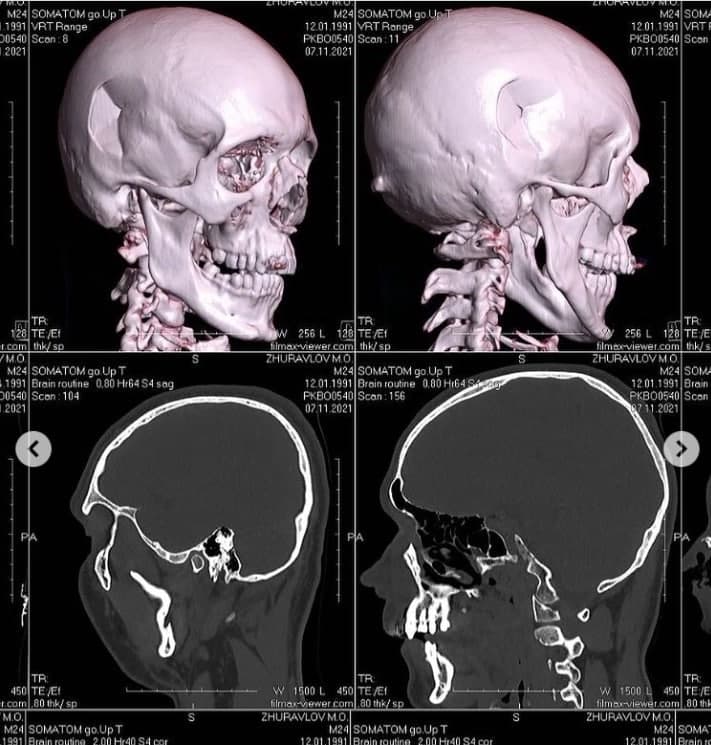

Композитора та музичного продюсера гурту KAZKA Миколу Журавльова побили у під’їзді його ж будинку. Лікарі діагностували переломи черепа та носу, а також травми підборіддя.

Каже, що вже переніс операцію з видалення пошкоджених кісток черепа. Надалі йому доведеться робити ще одну – ставитимуть титанову пластину.

"Хірург сказав, що з такими травмами зазвичай до лікарні приїжджають вже у комі. Але ми з Діаною ще 12 годин після травми їздили по всьому Києву робили обстеження, комп'ютерну томографію та інше", – пише Журавльов.

Згідно з висновками лікарів, у музиканта імпресійний перелом склепіння черепа в області скроневої та тім'яної кісток із вдавленням уламка у праву скроневу частку та перелом носових кісток.